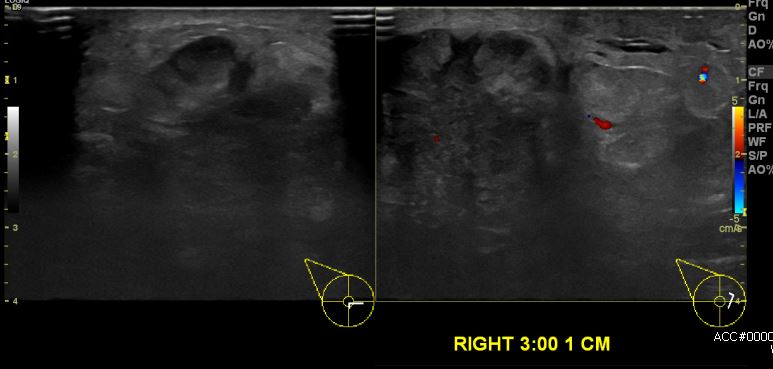

상기환자 건강검진상 이상 소견과 우측 유방의 만져지는 멍울로 내원하신 70대 여성분으로 우측 3시 방향에 만져지는 멍울 조직검사 시행하여 우측 침윤성 유관암 진단 되었습니다.